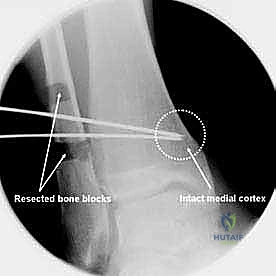

- قص العظم (Osteotomy): باستخدام منشار جراحي دقيق وموجهات خاصة، يتم قص عظم الظنبوب (وفي بعض الأحيان عظم الشظية أيضاً) بالزاوية التي تم تحديدها مسبقاً في التخطيط الثلاثي الأبعاد.

- تصحيح المحور: يتم فتح أو إغلاق الشق العظمي للوصول إلى المحور الميكانيكي السليم للكاحل. يتم التحقق من ذلك داخل غرفة العمليات باستخدام جهاز الأشعة السينية الفلوروسكوبي (C-arm).

| قطع العظم الإسفيني المغلق (Closing Wedge Osteotomy) | يتم إزالة مثلث (إسفين) صغير من العظم، ثم تُغلق الحواف على بعضها لتصحيح الزاوية. | التئام أسرع (عظم مقابل عظم مباشرة)، لا يحتاج لطعم عظمي. | يؤدي إلى قصر طفيف جداً في طول الساق، لا ينصح به للمرضى الذين يعانون من قصر الساق أصلاً. |